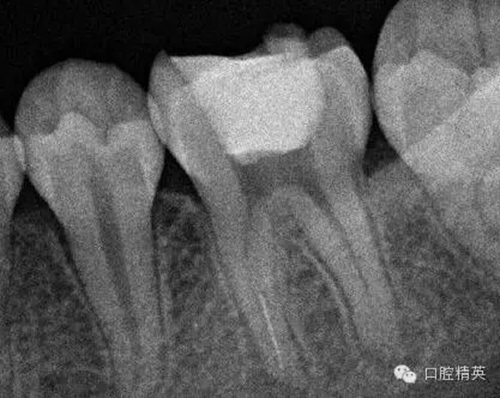

3,術(shù)前左下6近中根管斷針X-P,斷針長度約4MM,根尖慢性炎癥影像。。。